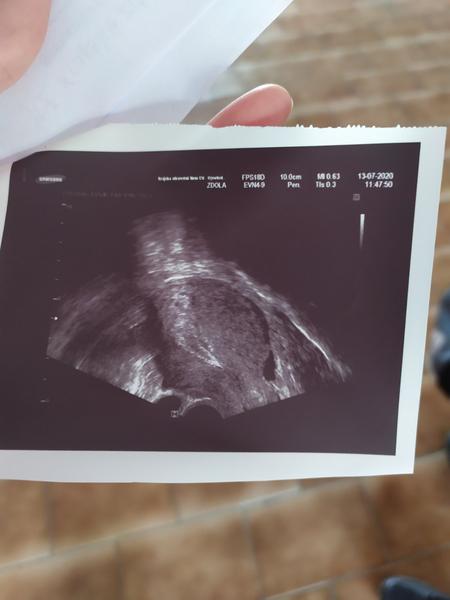

@veronikav31 krvácení nemám, bolesti občas jako na MS a občas mě bolí jakoby vaječníky,ale střídá se to, někdy v Levo někdy v pravo, dnes teda víc v právo...prodávám foto, co se na utz viděl..hodně malinkyho něco...

@kate013 ale tohle je ultrazvuk dělohy...tohle není mimoděložní těhotenství,to nejde na ultrazvuku vidět, hcg by rostlo moc pomalu a nic by vidět nebylo

@veronikav31 jako jestli jsem to dobře pochopila,tohle na fotce by teoreticky mohlo to těhotenství být....já nevím, jsem z toho zmatená :(

@kate013 ano,přesně tak, ta milinká tečka by měla znamenat těhotenství. toto je opravdu ultrazvuk dělohy, ne vejcovodu.A osobně já bych na vyčistění nešla, ne teď, určitě by bylo dobré nabrat znovu krev na hcg. já nechápu,proč doktoři posílají na vyčistění tak brzo. těhotenství může být mladší..

@veronikav31 teď jsem byla na příjmu u doktora, říkal,že 5mm něco tam je,že to těhotenství může být, ale že i nějaká tekutina v břiše,že to může být od cysty, já totiž bolesti nemám..takže zítra nic a ve středu ráno na lačno, odběr na hCG a kontrolní utz.kdyz to poroste a bude něco vidět, půjdu domů, když ne,tak na tu laparoskopii...za dva dny už by dutinka měla být větší,že?